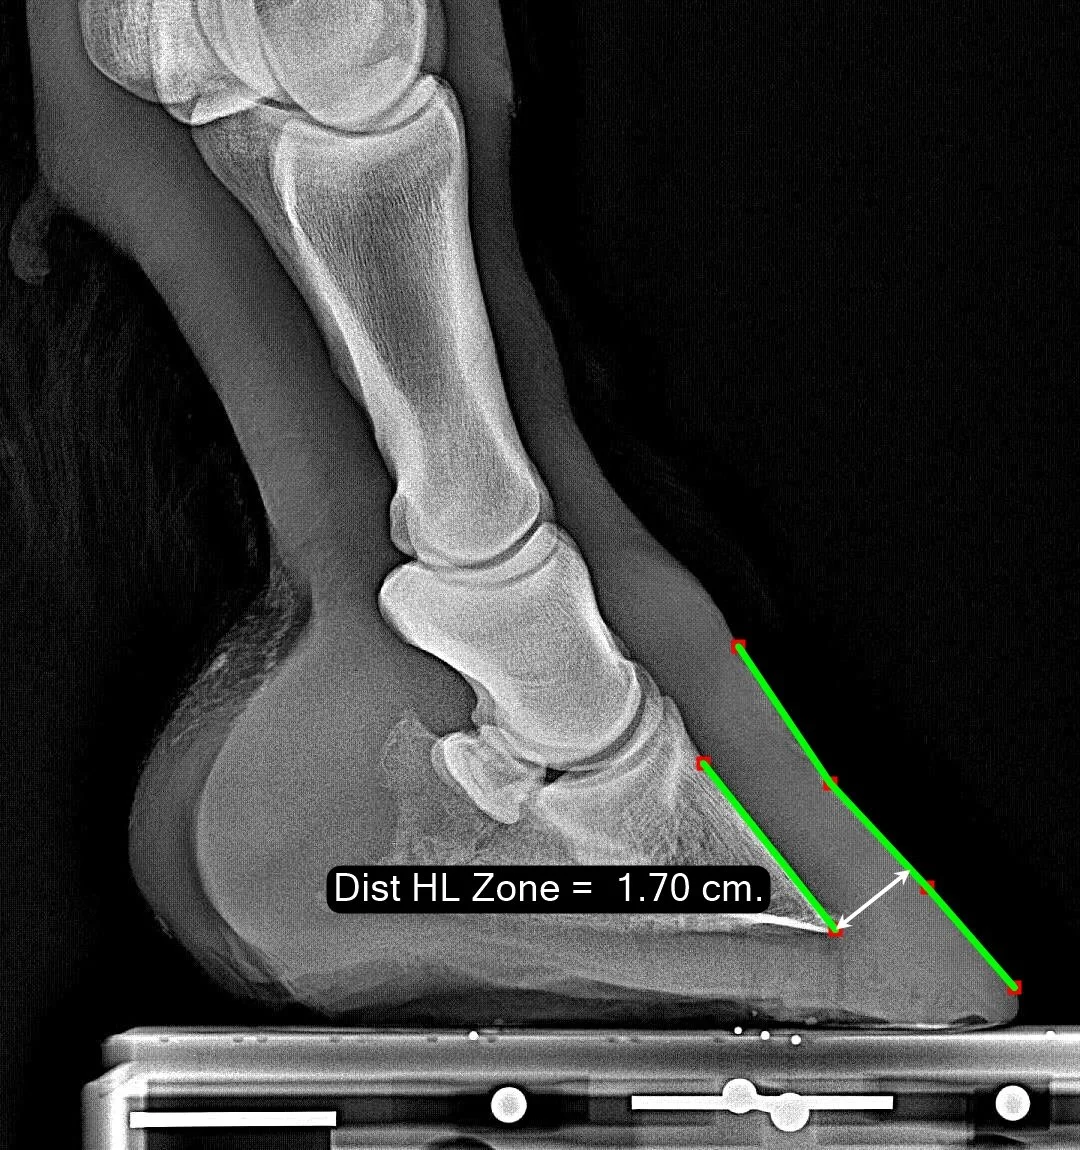

Distal HL Zone

The Distal Hoof-Lamellar (HL) Zone measures the distance from the dorsal aspect of the P3 bone at its tip out to the outer hoof wall. It is measured perpendicular to the face of P3.

Normal Range

Because this is a linear measurement, in our population distribution graph we divide the distance by the length of P2. For this example image, this yields the value 0.43. Our normal zone is from 0.34 to 0.57 with a median value of 0.44 - so this example is quite near the median. A normal value is 44% of the length of P2.